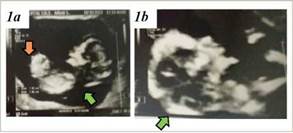

A las 12 semanas de gestación, se solicitó una ecografía de cribado para la detección de cromosomopatías y la prevención de preeclampsia. El informe ecográfico evidenció una gestación de 13 semanas, sin riesgo a preeclampsia por doppler de arterias uterinas y reveló la presencia de un higroma quístico (translucencia nucal de 11.1 mm) junto con un defecto de la pared abdominal compatible con onfalocele (VerFigura 1a y 1b).

Figura 1 1a) Corte longitudinal de cabeza, torax y abdomen donde se observa el higroma quístico (flecha verde) y el onfalocele (flecha naranja). 1b) Corte longitudinal de cabeza y cuello donde se observa el higroma quístico (flecha verde).